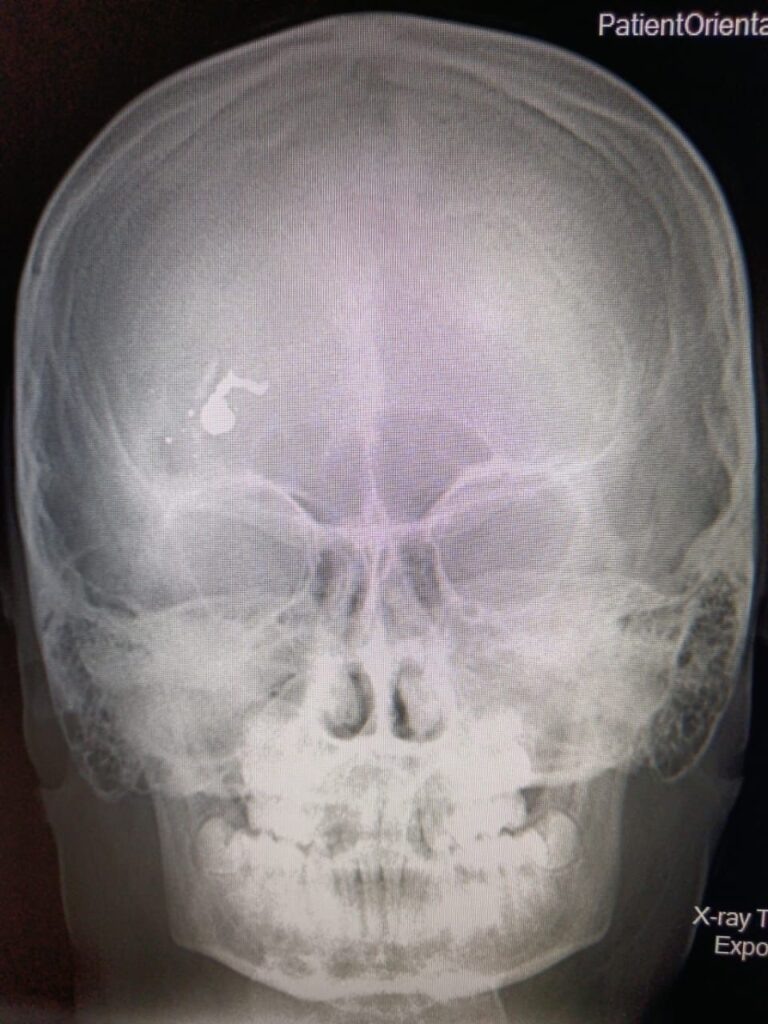

В Дергачевскую районную больницу был доставлен 12-летний мальчик, который при невыясненных обстоятельствах, получил огнестрельное ранение головы. Он был доставлен в детскую областную больницу, где операционная бригада незамедлительно приступила к операции, которая длилась около пяти часов. Об этом сообщило министерство здравоохранения саратовской области и опубликовало фото.

«В результате операции инородные тела (пуля с осколками) удалены. Тяжесть соответствует объёму проведенной операции, оперативное лечение выполнено в полном объёме, проводится наблюдение за ребенком. На данный момент мальчик пришел в сознание. Пожелаем ему скорейшей стабилизации состояния и выздоровления, а всем врачам Дергачевской районной больницы и Саратовской областной детской клинической больницы, принимавшим участие в оказании помощи и продолжающим это делать, спасибо! Так держать! Ваши молниеносные и слаженные действия сработали на результат», — прокомментировал министр здравоохранения Владимир Дудаков. Ерш

«В результате операции инородные тела (пуля с осколками) удалены. Тяжесть соответствует объёму проведенной операции, оперативное лечение выполнено в полном объёме, проводится наблюдение за ребенком. На данный момент мальчик пришел в сознание. Пожелаем ему скорейшей стабилизации состояния и выздоровления, а всем врачам Дергачевской районной больницы и Саратовской областной детской клинической больницы, принимавшим участие в оказании помощи и продолжающим это делать, спасибо! Так держать! Ваши молниеносные и слаженные действия сработали на результат», — прокомментировал министр здравоохранения Владимир Дудаков.

Ершовским межрайонным следственным отделом следственного управления СК России по Саратовской области проводится процессуальная проверка. Предварительно установлено, что 8 ноября 2024 года с места жительства, расположенного в р.п. Дергачи Дергачевского района, в медицинское учреждение госпитализирован мальчик с травмой, полученной от пневматической винтовки.